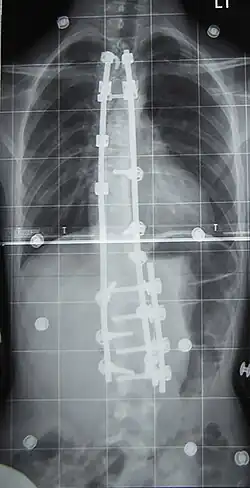

L'indication concerne environ 10 % des scolioses idiopathiques du sujet jeune[2] et concerne les scolioses importantes, avec un angle de Cobb dépassant les 50°. La technique consiste en la mise en place de deux longues tiges métalliques vissées dans les vertèbres, permettant le redressement de la colonne vertébrale, notamment avec la technique et le matériel de 3e génération proposés par Cotrel et Dubousset[45]. Les complications sont essentiellement locales mais il peut exister des étirements ou compressions de racines nerveuses dans moins d'un pour cent des interventions[46].

À l'issue de l'intervention (qui peut dans certains cas corriger totalement la scoliose), le rachis est bloqué de manière définitive. Les vertèbres libres de greffe devant travailler davantage pour « compenser » l'immobilisation du reste de la colonne, des douleurs dans le dos peuvent apparaître de façon imprévisible et à tout âge. Le rachis étant un flexible conçu pour bouger - et non être bloqué, on considère que l'opération ne règle pas entièrement le problème : on supprime un défaut (la courbure) pour en créer un nouveau : la rigidité du dos liée à l'opération